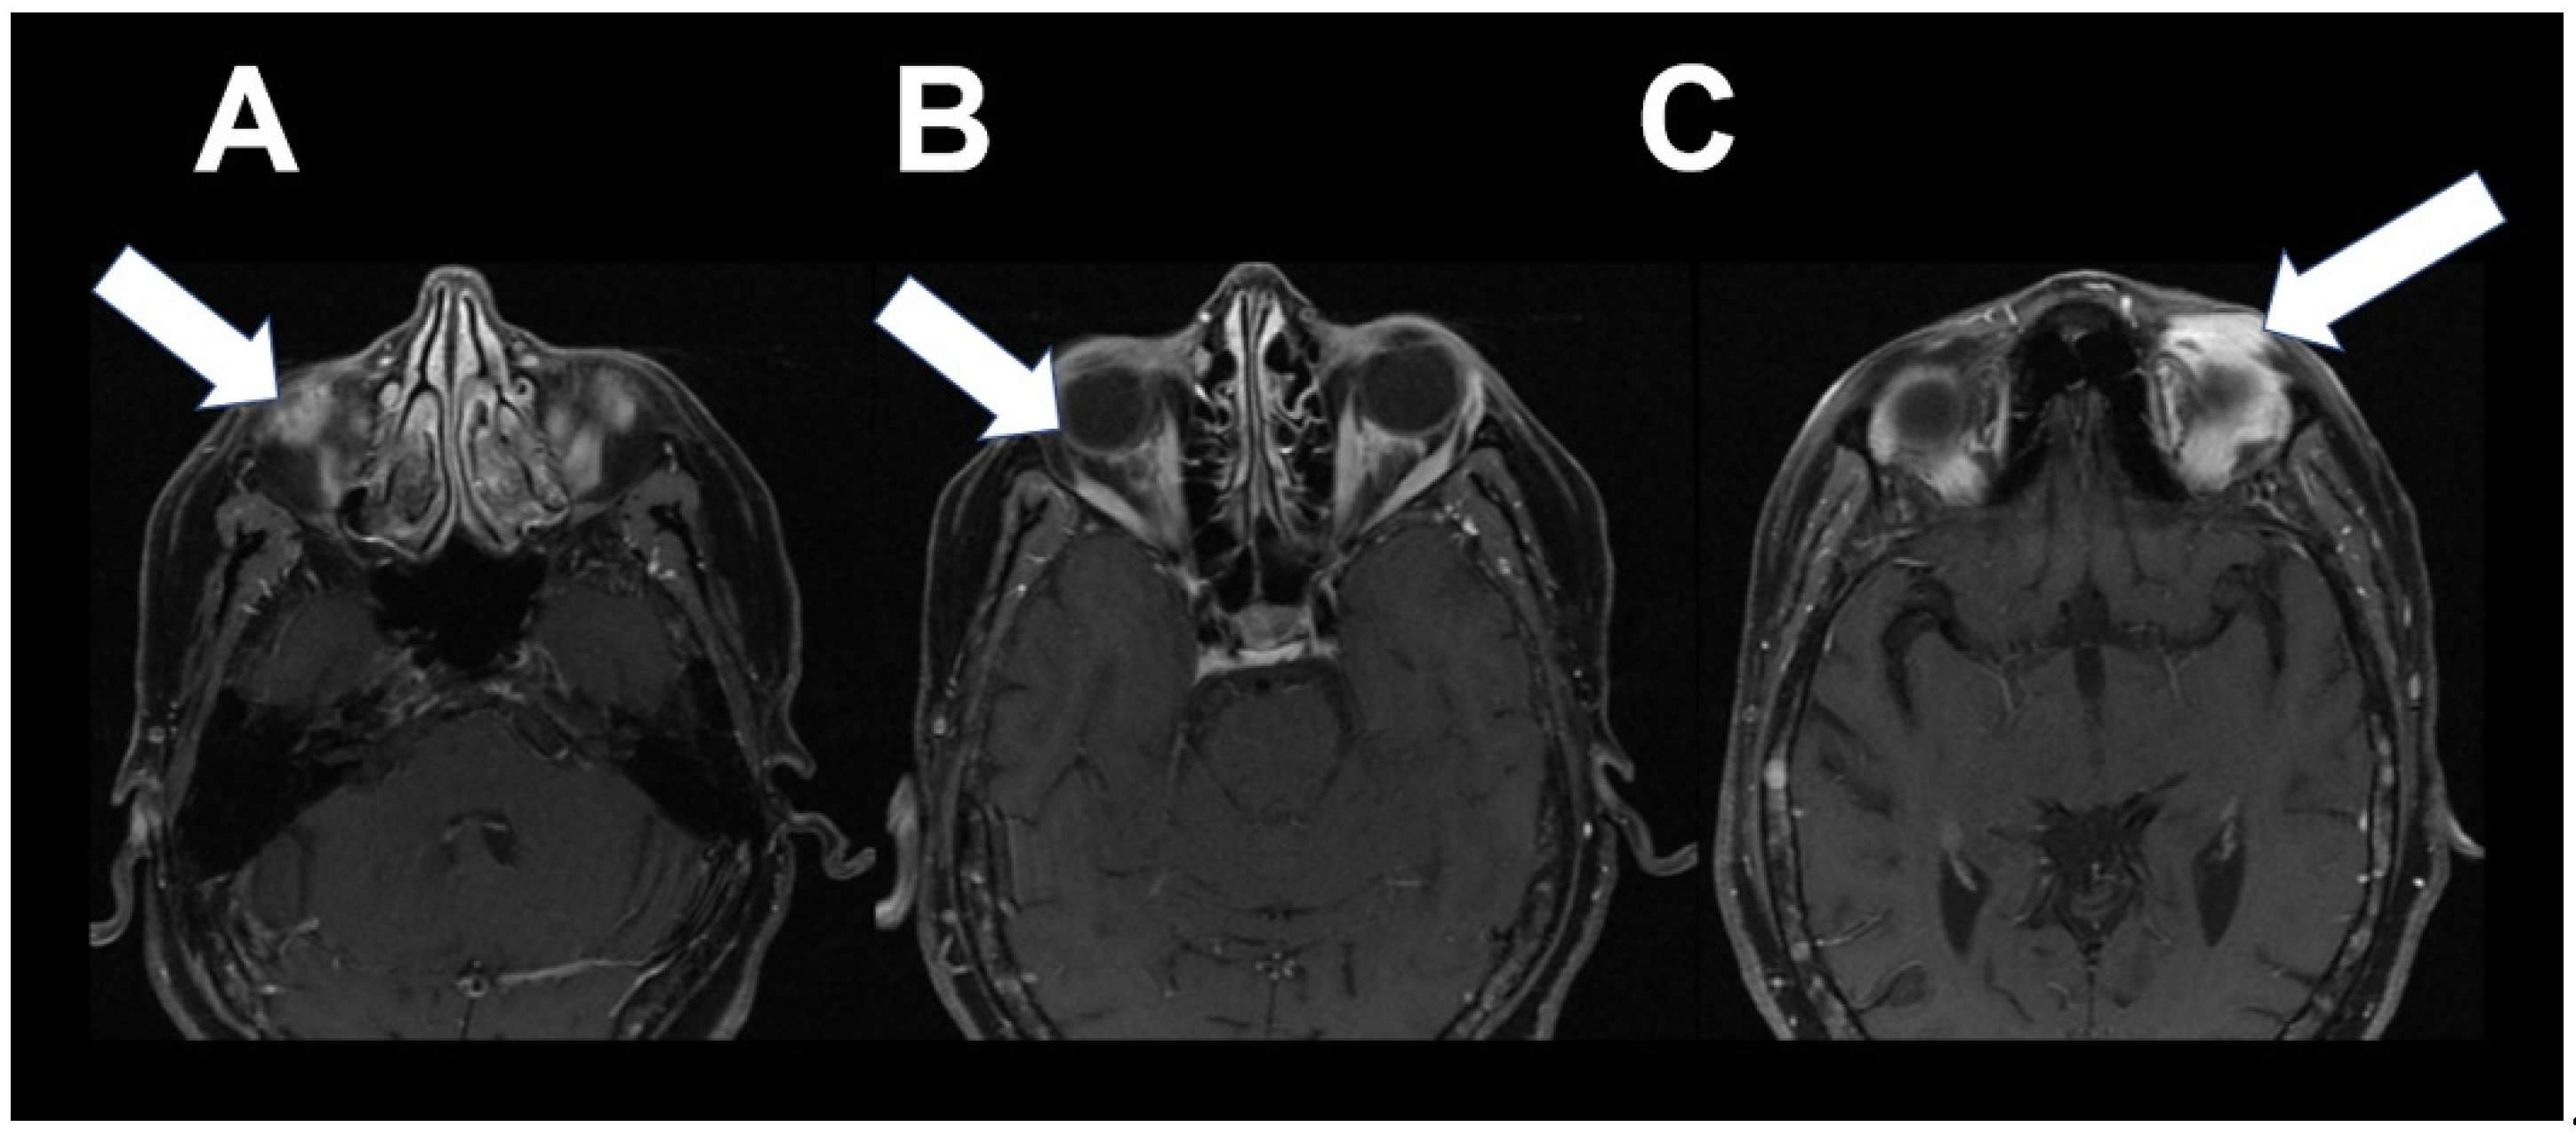

3. Case 2